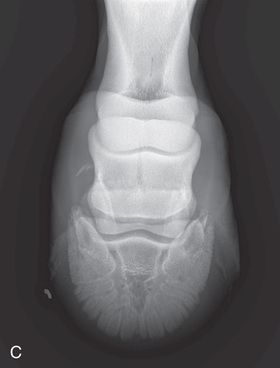

Digit/foot: P-III (distal phalanx, coffin bone) P-II (middle phalanx) P-I (proximal phalanx-pastern) Proximal interphalangeal joint (pastern joint) joint | DP (Standard) (Fig. 24.62B,C) | Dorsal 45-degree proximal–palmarodistal (D45Pr-PaDi) | Foot slightly forward on image receptor. | Perpendicular to foot axis at MSP (midsagittal plane) at area of interest with beam angled ~45 degrees to ground |

| Lateral (Standard) (Fig. 24.62D) | Lateromedial | On a block to elevate limb for P-III; resting on ground for other views. | 90 degrees lateral to MSP, parallel to ground on area of interest: coronary band for PIII | |